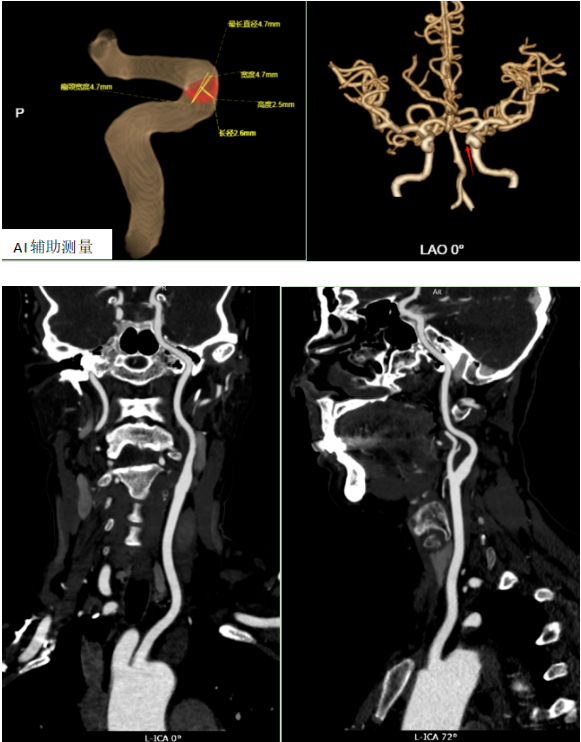

CTA图像清晰显示:左颈内动脉C5段有一处瘤样凸起,形态符合“小动脉瘤”的典型表现。在AI辅助测量下,瘤体的大小、形态、与血管的关系被精确量化,为后续治疗提供了关键依据。

在本病例中,患者通过MRA初筛,再经CTA确认,结合AI辅助测量,实现了精准、无创、高效的诊断流程。